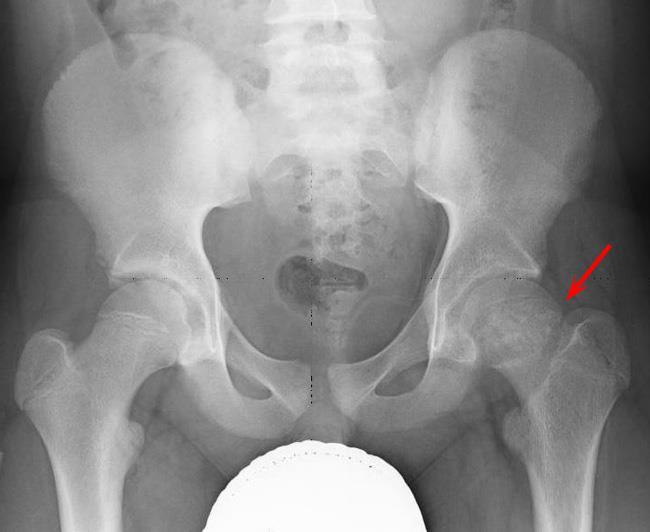

A patient presents with this gait two weeks after an intramuscular buttocks injection. What is this sign? What is likely the cause?

Trendelenberg sign: pelvis tilts with walk because weight-bearing leg cannot maintain balance

Caused by superior gluteal nerve injury secondary to IM injection too medially on buttocks.

This nerve supplies abductor muscles of hip.

KEY POINT: IM injections in buttocks should be given in upper outer quadrant to avoid superior gluteal nerve or sciatic nerve injury